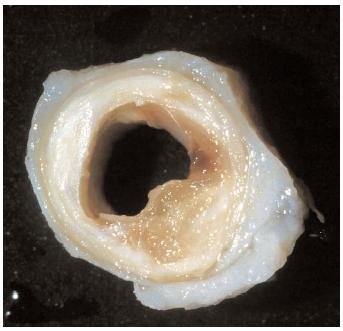

Вот так выглядит сосуд, поражённый атеросклерозом